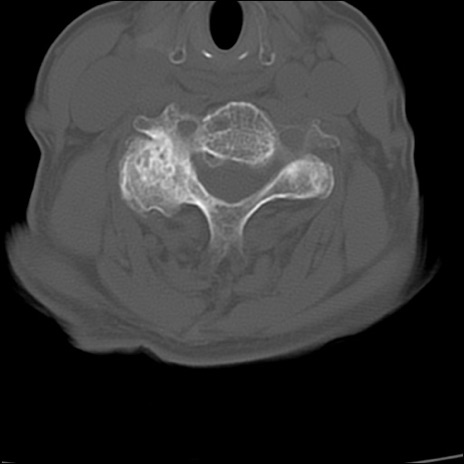

頚椎CT